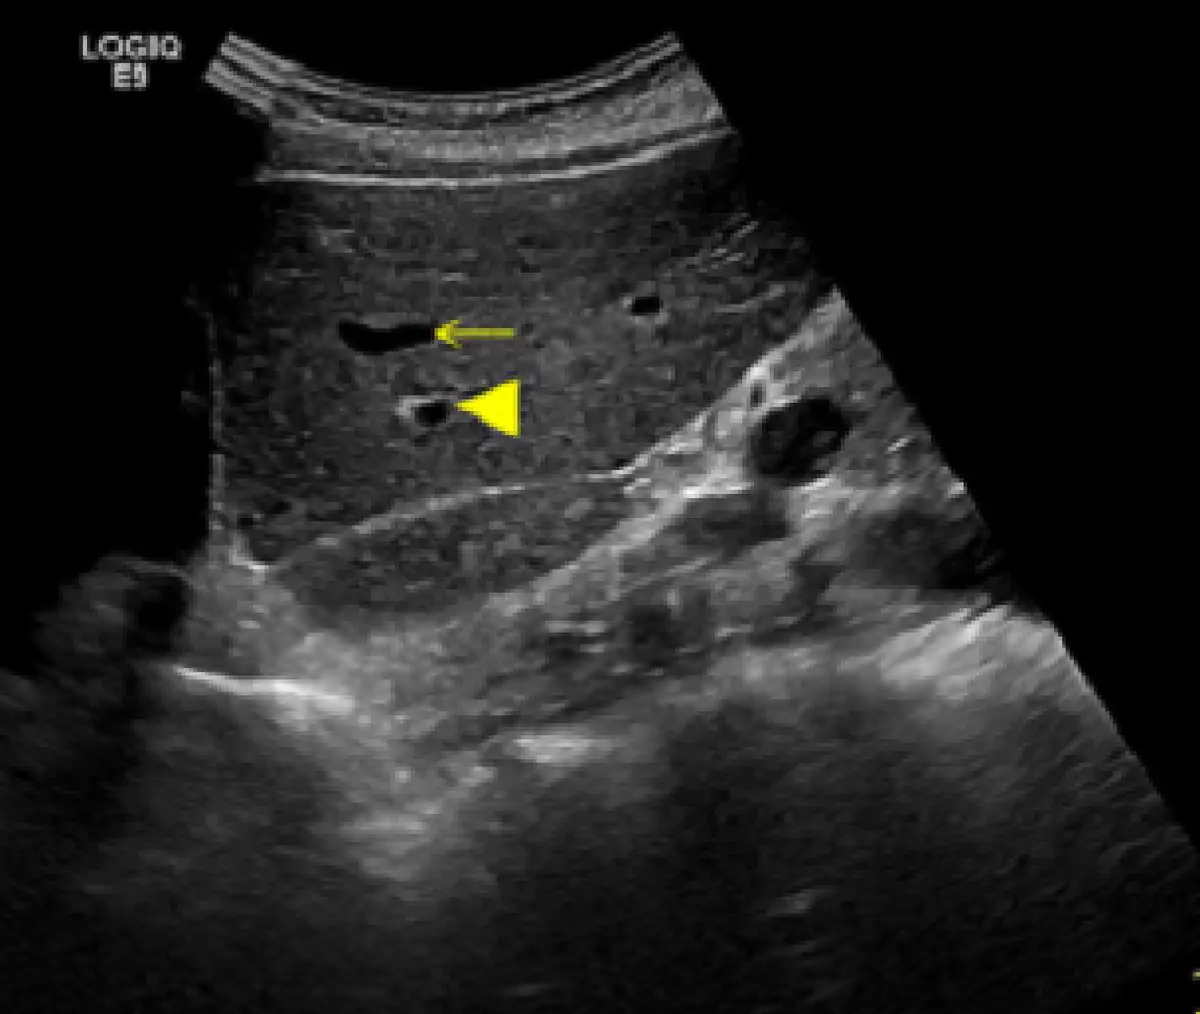

附圖為肝臟超音波影像,箭頭( ◄)以及箭號( ←)所指分別為何?

本題影像為 GE LOGIQ E9 超音波儀器所取得的肝臟橫切面(transverse/oblique)灰階超音波影像。影像中央可見兩個無回音(anechoic)的圓形管狀截面,各有不同的標記符號:

箭頭符號(◄,arrowhead,填實三角形):指向位置較下方的管狀結構,管壁可見明顯高回音(hyperechoic wall),壁厚且邊緣清晰、明亮。此為 門靜脈(portal vein) 的典型超音波特徵——因門靜脈壁含有 Glisson 氏囊(Glisson's capsule)的纖維脂肪組織,在廣泛的聲波入射角度下均呈高回音。

箭號符號(←,arrow,一般箭頭):指向位置較上方的管狀結構,管壁薄且回音較低(thin, relatively hypoechoic wall),邊緣較不清晰。此為 肝靜脈(hepatic vein) 的典型超音波特徵——因肝靜脈壁主要由緊密平行排列的膠原纖維組成,屬於鏡面反射體(specular reflector),僅在聲束與血